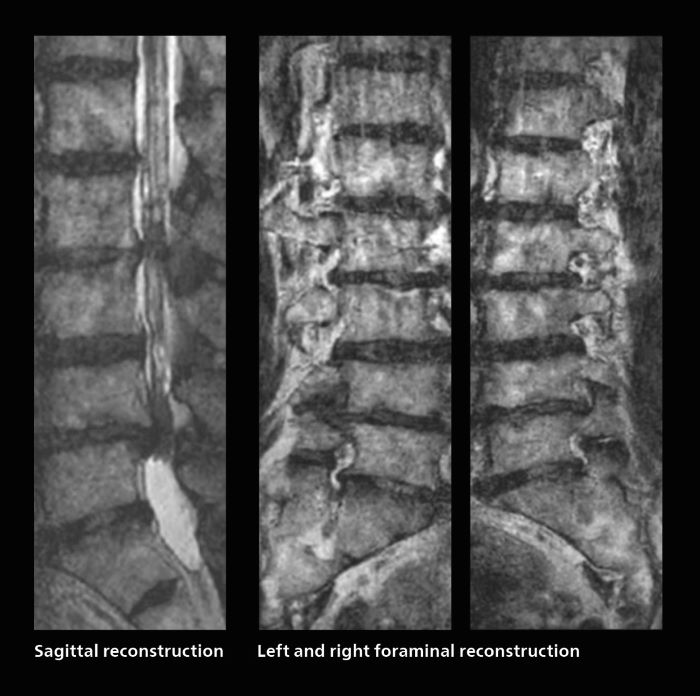

Faster lumbar spine exams are beneficial for patients with pain

Many patients who must undergo a lumbar spine examination suffer from back pain. For these patients it is difficult to maintain the imaging position long enough to successfully complete the examination. “In such cases, using SmartSpeed allows us to perform volume imaging, so that we acquire only one high resolution 3D sequence in a short time and then reconstruct the other orientations from that,” Dr. Katahira says.

“This is highly advantageous because the patient needs only endure a short exam time, whereas before it was necessary to acquire a larger number of sequences in total. We have seen that the shorter time has allowed us to scan patients who previously could not finish the exam. This is a great advantage.”

Fast lumbar spine imaging for successful exam of patient in pain

A patient arrived saying that undergoing MRI was not possible because of severe back pain and leg pain, was imaged with SmartSpeed in only 94 seconds. The scan was diagnostic and afterwards the patient confirmed that it only took a little while. Performed on Elition X.

The hospital’s fast lumbar spine ExamCard includes T2W SpineVIEW, 1:40 min, 1.0 mm isotropic, acceleration factor 12.